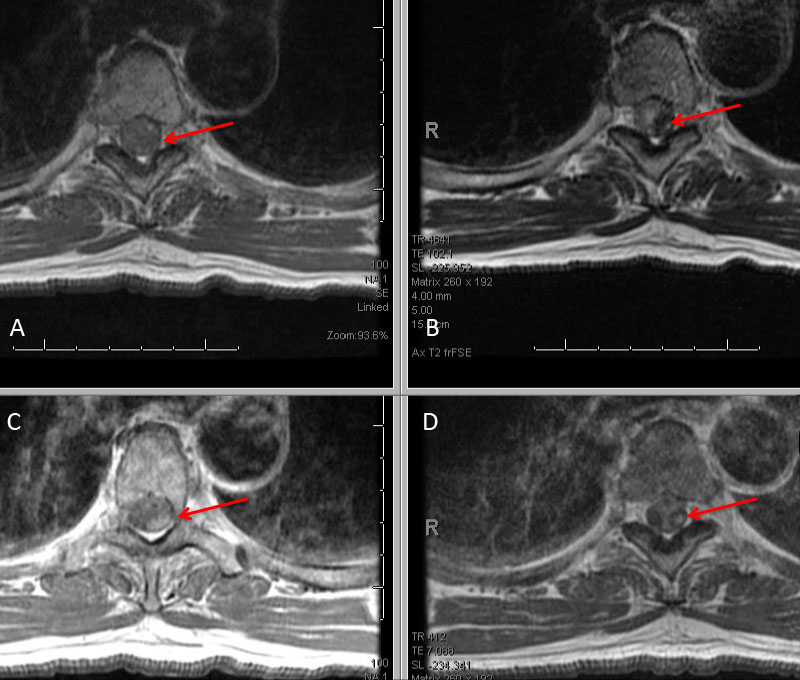

The subararachnoid hemorrhage was focused primarily within the spinal axis of the cervical thoracic and lumbar spine with secondary extension into the brain. A suspicious focal hematoma or mass was observed within the left T4-T5 region with local mass effect representing an intradural extra medullary abnormality with secondary compression of the cord and central myelopathic T2 signal abnormality (Figure 2. A,B,C,D).

Figure 2: A) T1 B) C+ T1 C) STIR D) FS C+ T1 demonstrate focal hemorrhage, contrast enhancement, mass effect, and myelopathic cord signal at T4 (arrows)